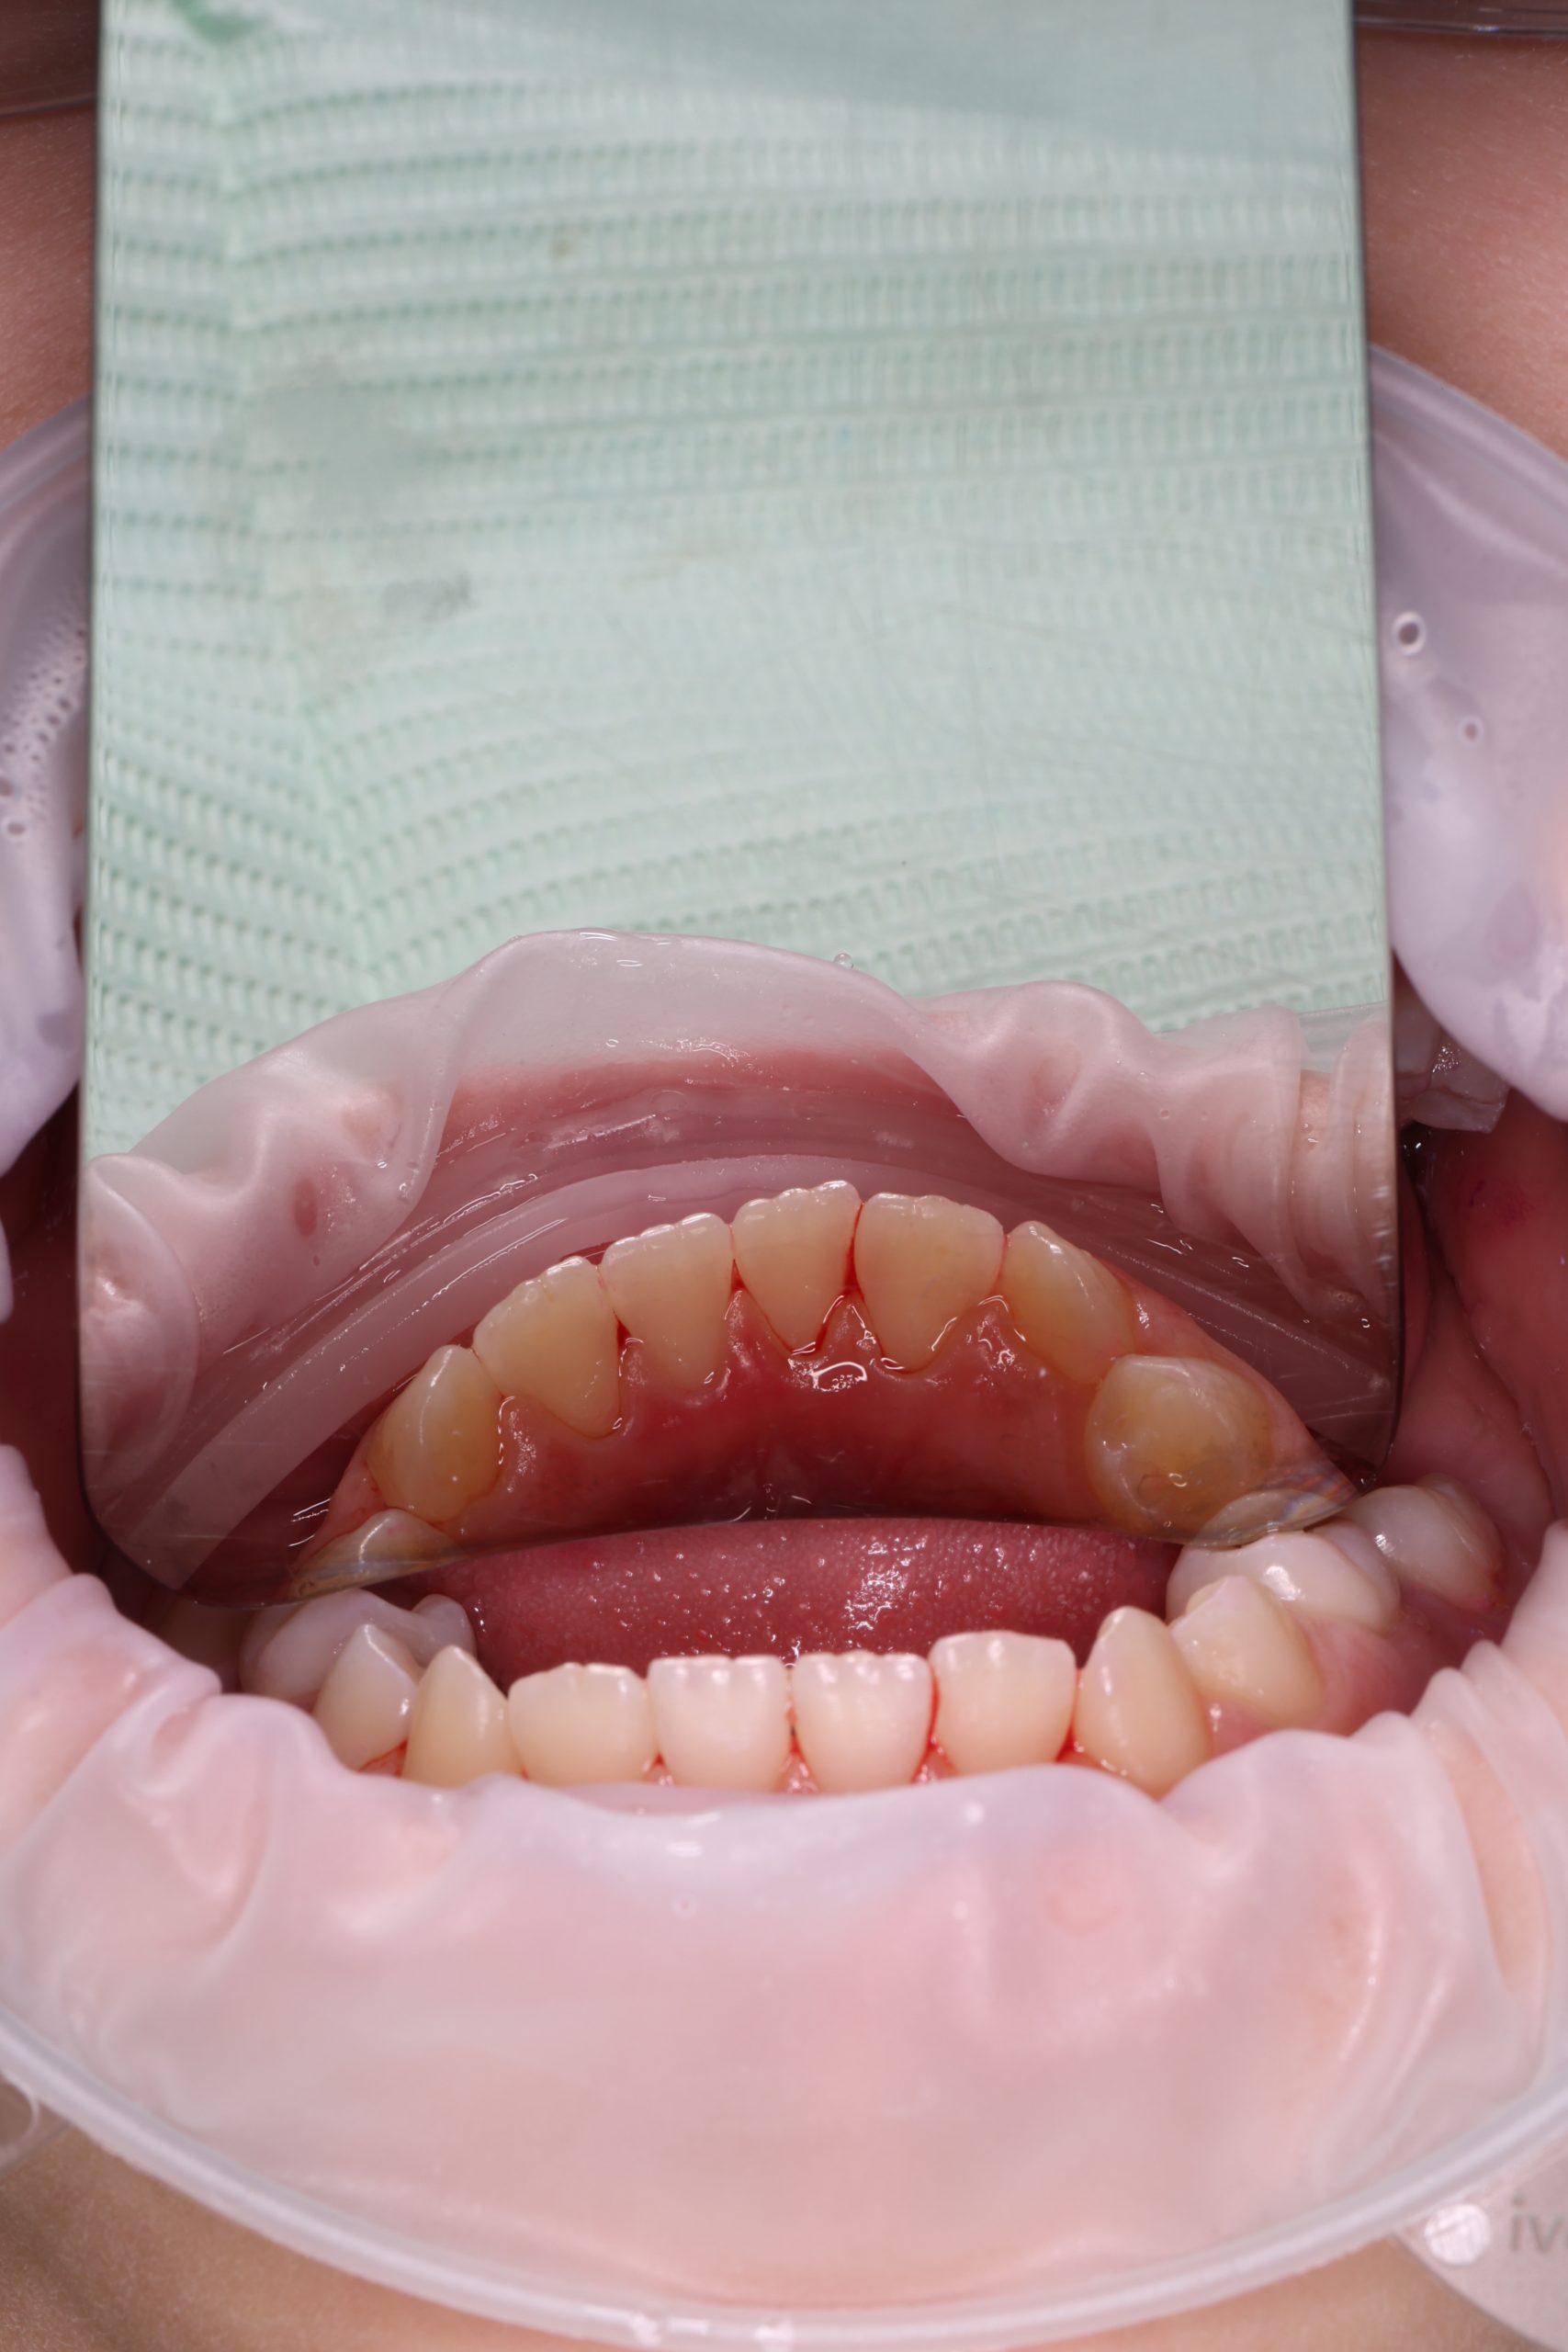

Together with your child, we practice brushing techniques, correct mistakes, and provide personalized recommendations. We advise whether to use manual or electric brushes, floss, interdental brushes, or remineralizing gels. - Plaque Removal with AIRFLOW Prophylaxis Master (EMS, Switzerland)

From age 4–5 and up, we perform full GBT cleaning using an ultra-fine erythritol powder to clean even hard-to-reach areas gently and safely. It does not damage enamel and is ideal even around braces — no need to remove brackets or wires. - Tartar Removal (If Needed)